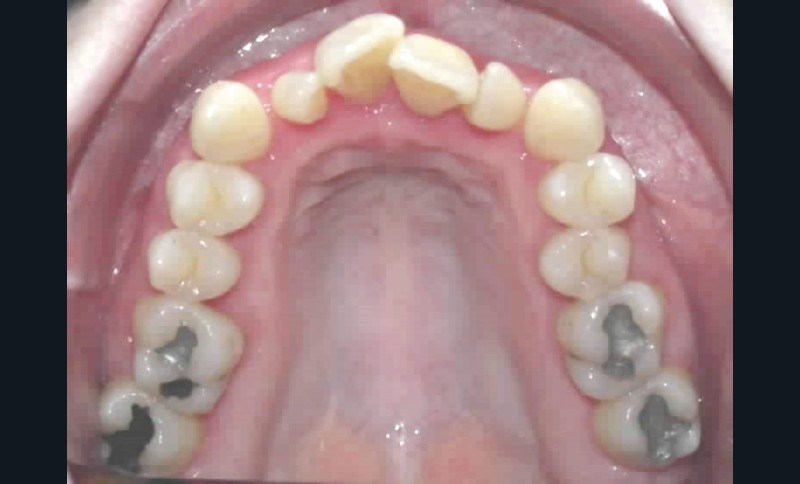

• fortes malpositions des incisives supérieures (dont 22 qui est en rotation axiale disto-palatine de 90°), • dysharmonie dento-dentaire (12 en « grain de riz » est aussi en rotation marginale disto-palatine de 45°),

• anomalie de la forme d’arcade maxillaire, 47, 18 et 28 sont absentes. (fig. 1 à 8), 48 est positionnée très postérieurement, quasiment au niveau de la branche montante (fig. 9 et 11).

Après assainissement parodontal, un traitement par expansion maxillaire avec vestibuloversion des incisives supérieures et mésialisation de 48 en lieu et place de 47 a été choisi. Il a été décidé d’extraire 38. Afin de permettre une reconstitution prothétique pour compenser la microdontie de 12 il est prévu de laisser un espace de part et d’autre de celle-ci, équivalent au diamètre mésio-distal de 22 soit 6,5 mm.